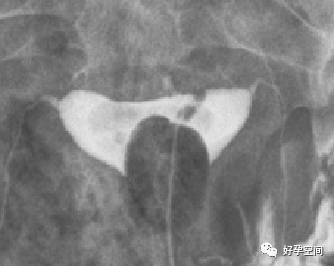

5、正常输卵管走行:正常的输卵管是从子宫角的尖端起,呈自然流线形,输卵管走行不固定,两侧输卵管不一定对称,输卵管活动度很大,走行分四型:(1)上行,和宫体连接呈缠绕状,在子宫底两侧弯弯曲曲上行,壶腹部远段和伞部向下屈曲。(2)反向走行,一侧上行,另一侧下行。(3)下行,和宫体连接呈缠绕状,在子宫两侧弯弯曲曲下行,壶腹部远段和伞部向上屈曲。(4)水平走行,在宫底水平向两侧呈伸展状。

双侧输卵管上行

双侧输卵管反向走行(一侧上行,对侧下行)

双侧输卵管下行

双侧输卵管水平走行